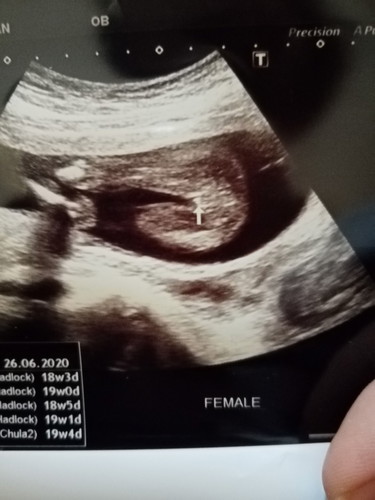

อยากทราบว่ามีใครพอจะรุ้ไหมค่ะว่าน้องเพศหญิงรึชายค่ะ

น่าจะหญิงค่ะ